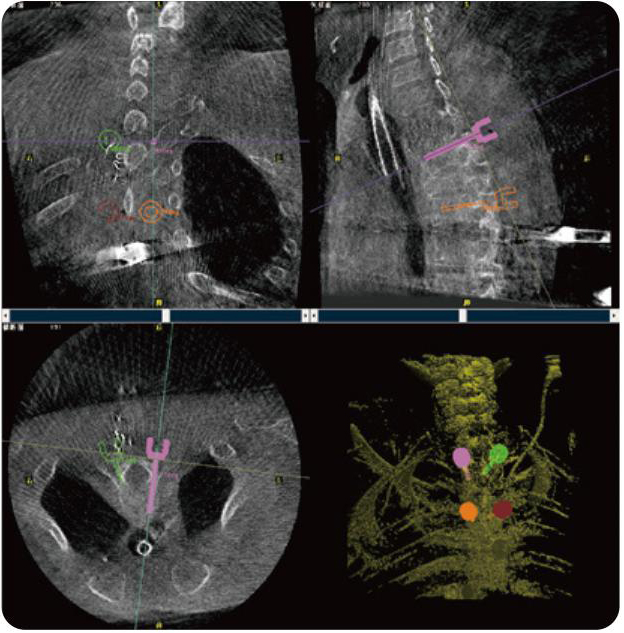

PL300B可應用于多節(jié)段脊柱外科手術,輔助醫(yī)生定位病灶部位,為脊柱外科手術(經(jīng)皮椎體成形術、椎弓根螺釘內(nèi)固定術等術式)提供術前手術流程規(guī)劃、入釘位置、角度可視化引導,模擬仿真入釘輔助。

PL300B搭配普愛醫(yī)療自主研發(fā)生產(chǎn)的平板3D C形臂,借助一體化自適應配準( 軌跡配準)技術,通過追蹤C形臂三維采集軌跡,自動完成圖像坐標建立和系統(tǒng)坐標配準。配準精度更高,操作步驟少,系統(tǒng)運作效率高。